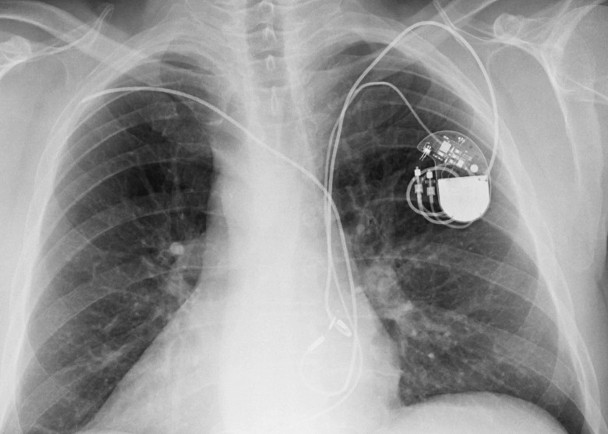

美國國土安全部(DHS)日前發表報告,稱多達75萬個植入式心臟除顫器出現保安漏洞,有機會受黑客攻擊。這批器材均由醫療科技公司美敦力(Medtronic)製造,為降低風險,該公司已採取措施監測,並加強網上安全規範。

美媒報道,美敦力所生產的20種產品容易受黑客攻擊,包括植入式心臟除顫器。報道指,要操控除顫器或獲得使用者數據,不需要太複雜的技術,只要能夠進入Conexus遙測系統,就有機會傷害病人。由於該系統缺乏加密功能,也不需身份驗證或取得授權,黑客有機會作干擾。